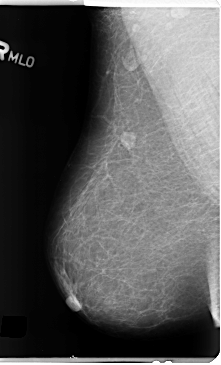

ics_version 1.0 filename B-3153-1 DATE_OF_STUDY 13 5 1998 PATIENT_AGE 69 FILM FILM_TYPE REGULAR DENSITY 1 DATE_DIGITIZED 21 4 1998 DIGITIZER LUMISYS LASER SEQUENCE LEFT_CC LINES 4688 PIXELS_PER_LINE 2720 BITS_PER_PIXEL 12 RESOLUTION 50 OVERLAY LEFT_MLO LINES 4688 PIXELS_PER_LINE 2776 BITS_PER_PIXEL 12 RESOLUTION 50 OVERLAY RIGHT_CC LINES 4728 PIXELS_PER_LINE 2760 BITS_PER_PIXEL 12 RESOLUTION 50 NON_OVERLAY RIGHT_MLO LINES 4736 PIXELS_PER_LINE 2872 BITS_PER_PIXEL 12 RESOLUTION 50 NON_OVERLAY |